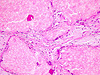

Caso 1.Paciente homem, 41 anos, lesão em cavidade oral

Paciente homem, 36 anos, tumor em mucosa jugal há 3 anos.

Paciente homem, 22 anos, tumor em parótida com duas recidivas anteriores.